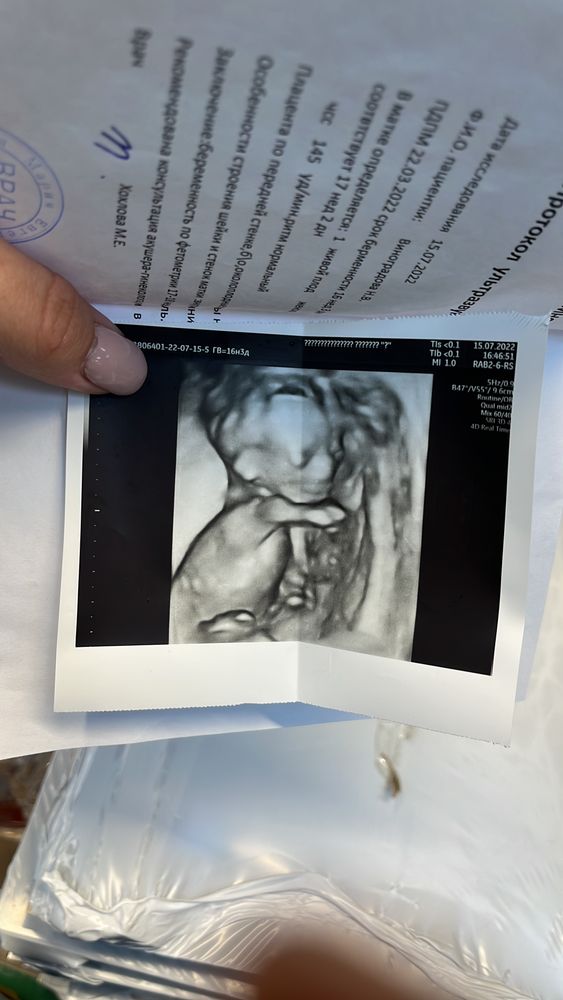

Узи в 17 недель (фото)??

Лучше ближе к 30 неделям, там уже будет похож на себя малыш. Вот например 30 недель, после рождения и в 10 месяцев Изображение